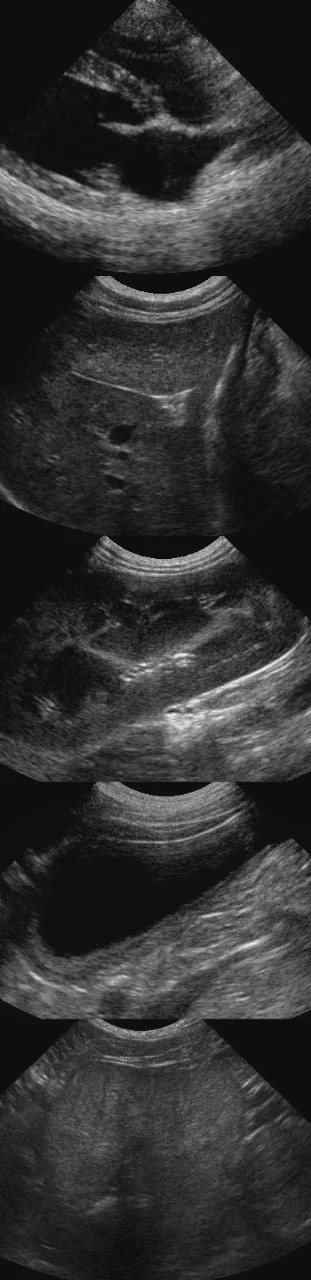

Veterinary ClinicLakeland Veterinary Imaging provides advanced diagnostic imaging (radiograph interpretation, PennHIP/OFA, and diagnostic ultrasound) for veterinary patients in WI.